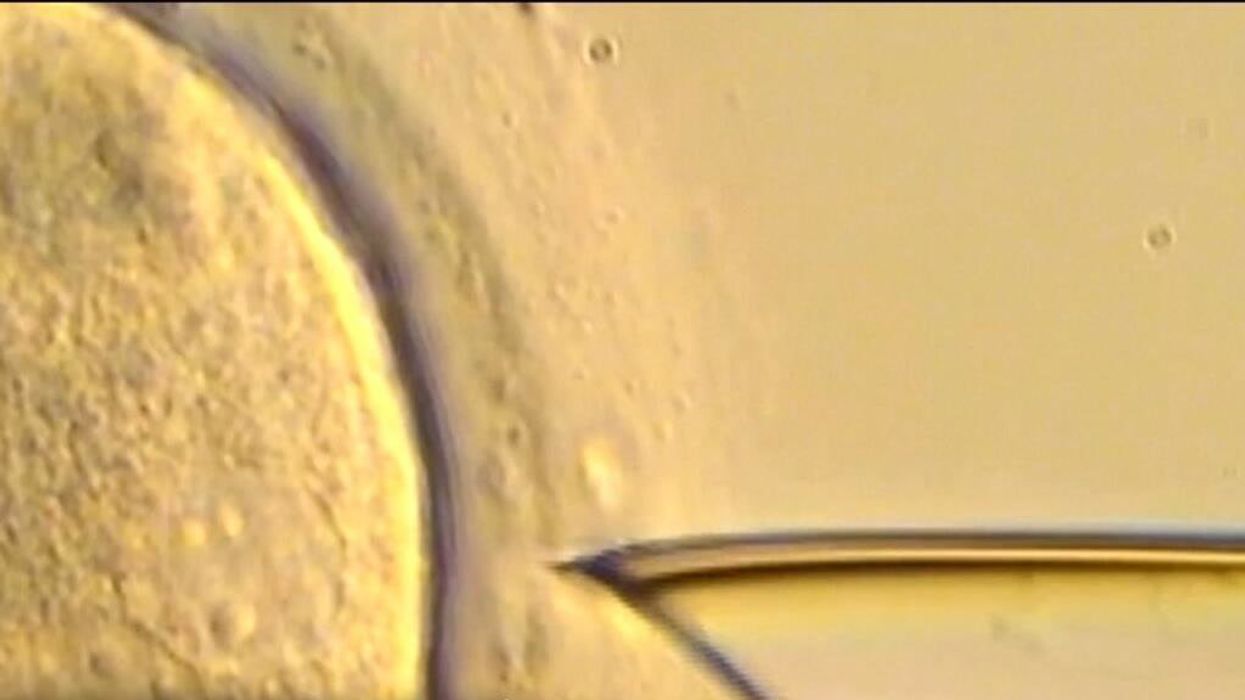

In vitro fertilisation (IVF) works by replicating the process of an egg and sperm successfully marrying together outside of the body, before being implanted into the uterus. It's long been a popular method of conception, particularly for those who would struggle to conceive otherwise.